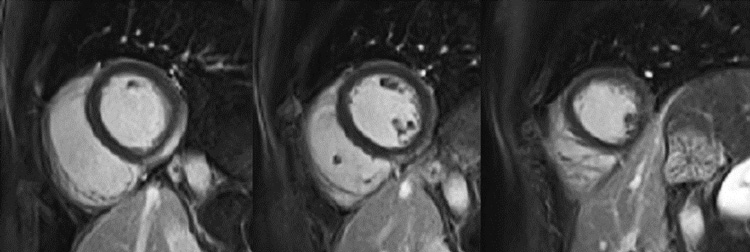

Figure 1A : Séquence Ciné-IRM - Coupes petit-axe basal

Figure 1B : Séquence Ciné-IRM - Coupes petit-axe médian

Figure 1C : Séquence Ciné-IRM - Coupes petit-axe apical

Figure 1D : Séquence Ciné-IRM - Coupes 2-cavités

Figure 1E : Séquence Ciné-IRM - Coupes 3-cavités

Figure 1F : Séquence Ciné-IRM - Coupes 4-cavités